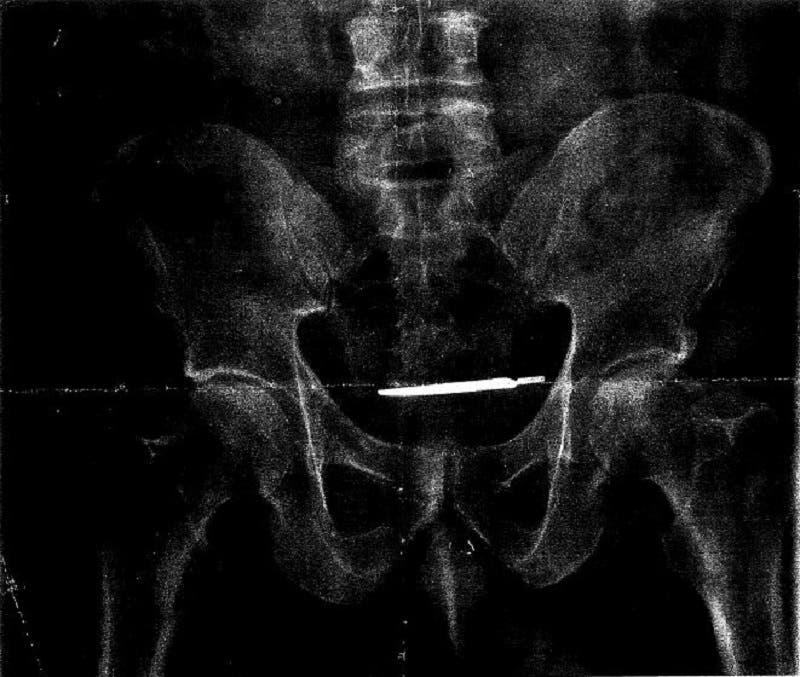

A scalpel was discovered inside a U.S. Army veteran's abdomen four years after a surgery at the West Haven VA, according to a lawsuit.

WEST HAVEN, CT — A U.S. Army veteran is suing the West Haven Veterans Affairs Hospital on allegations that his long-term abdominal pain was due to a scalpel that was left inside his body during a surgery at the hospital four years earlier, according to his attorney. New Haven-based Faxon Law Group filed a malpractice lawsuit against the VA Connecticut Healthcare System on Monday on behalf of Glenford Turner, 61, after an X-ray showed there was a scalpel inside his abdomen.

An X-ray revealed that there was a scalpel inside Turner’s body, which Faxon said doctors confirmed was the scalpel knife used during Turner’s radical prostatectomy — performed four years earlier at the West Haven VA — on Aug. 30, 2013.

Image via Faxon Law Group